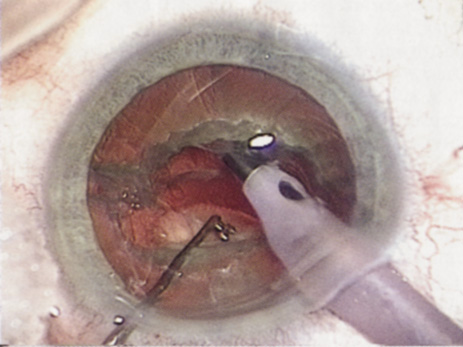

Back to Top